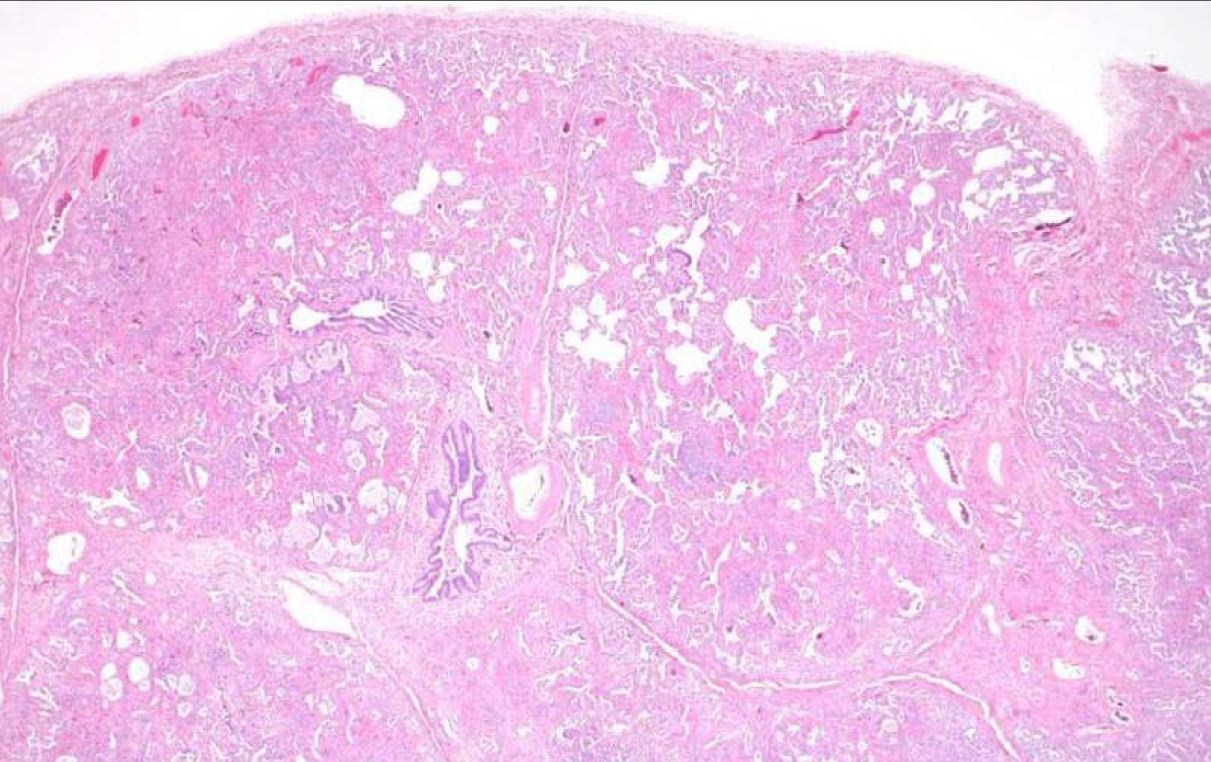

This lesion in the lung is seen more commonly in women with an average age in the 40s and shows papillary like projections lined by epithelioid cells with a central proliferation of polygonal mesenchymal appearing cells. Both populations are TTF1 positive indicating type II pneumocyte origin for this tumor.

Sclerosing hemangioma of the lung